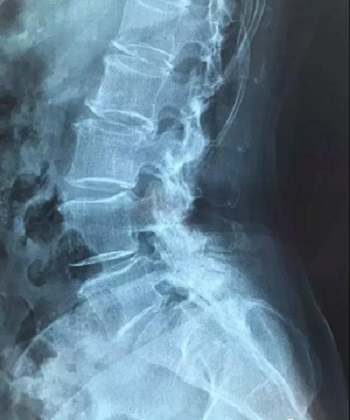

十、因此需要将磁共振的一张片子,进行分区域局部放大拍摄,尽可能的将片子上的细节拍摄清楚,将一张磁共振片子进行分区。

十一、将分区的磁共振图像,按顺序进行拍摄,即可获取如下比较有价值的清晰图片